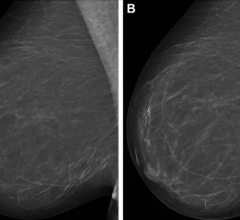

To use the system, the healthcare practitioner simply palpates suspicious breast lesions with the hand-held tactile probe, which employs highly sensitive sensors clinically proven to map lesions as small as 5 mm. The portable SureTouch console creates an electronic record that provides a wealth of objective information to help recognize suspicious lesions and make informed recommendations for follow-up radiological diagnostics such as mammography and ultrasound.